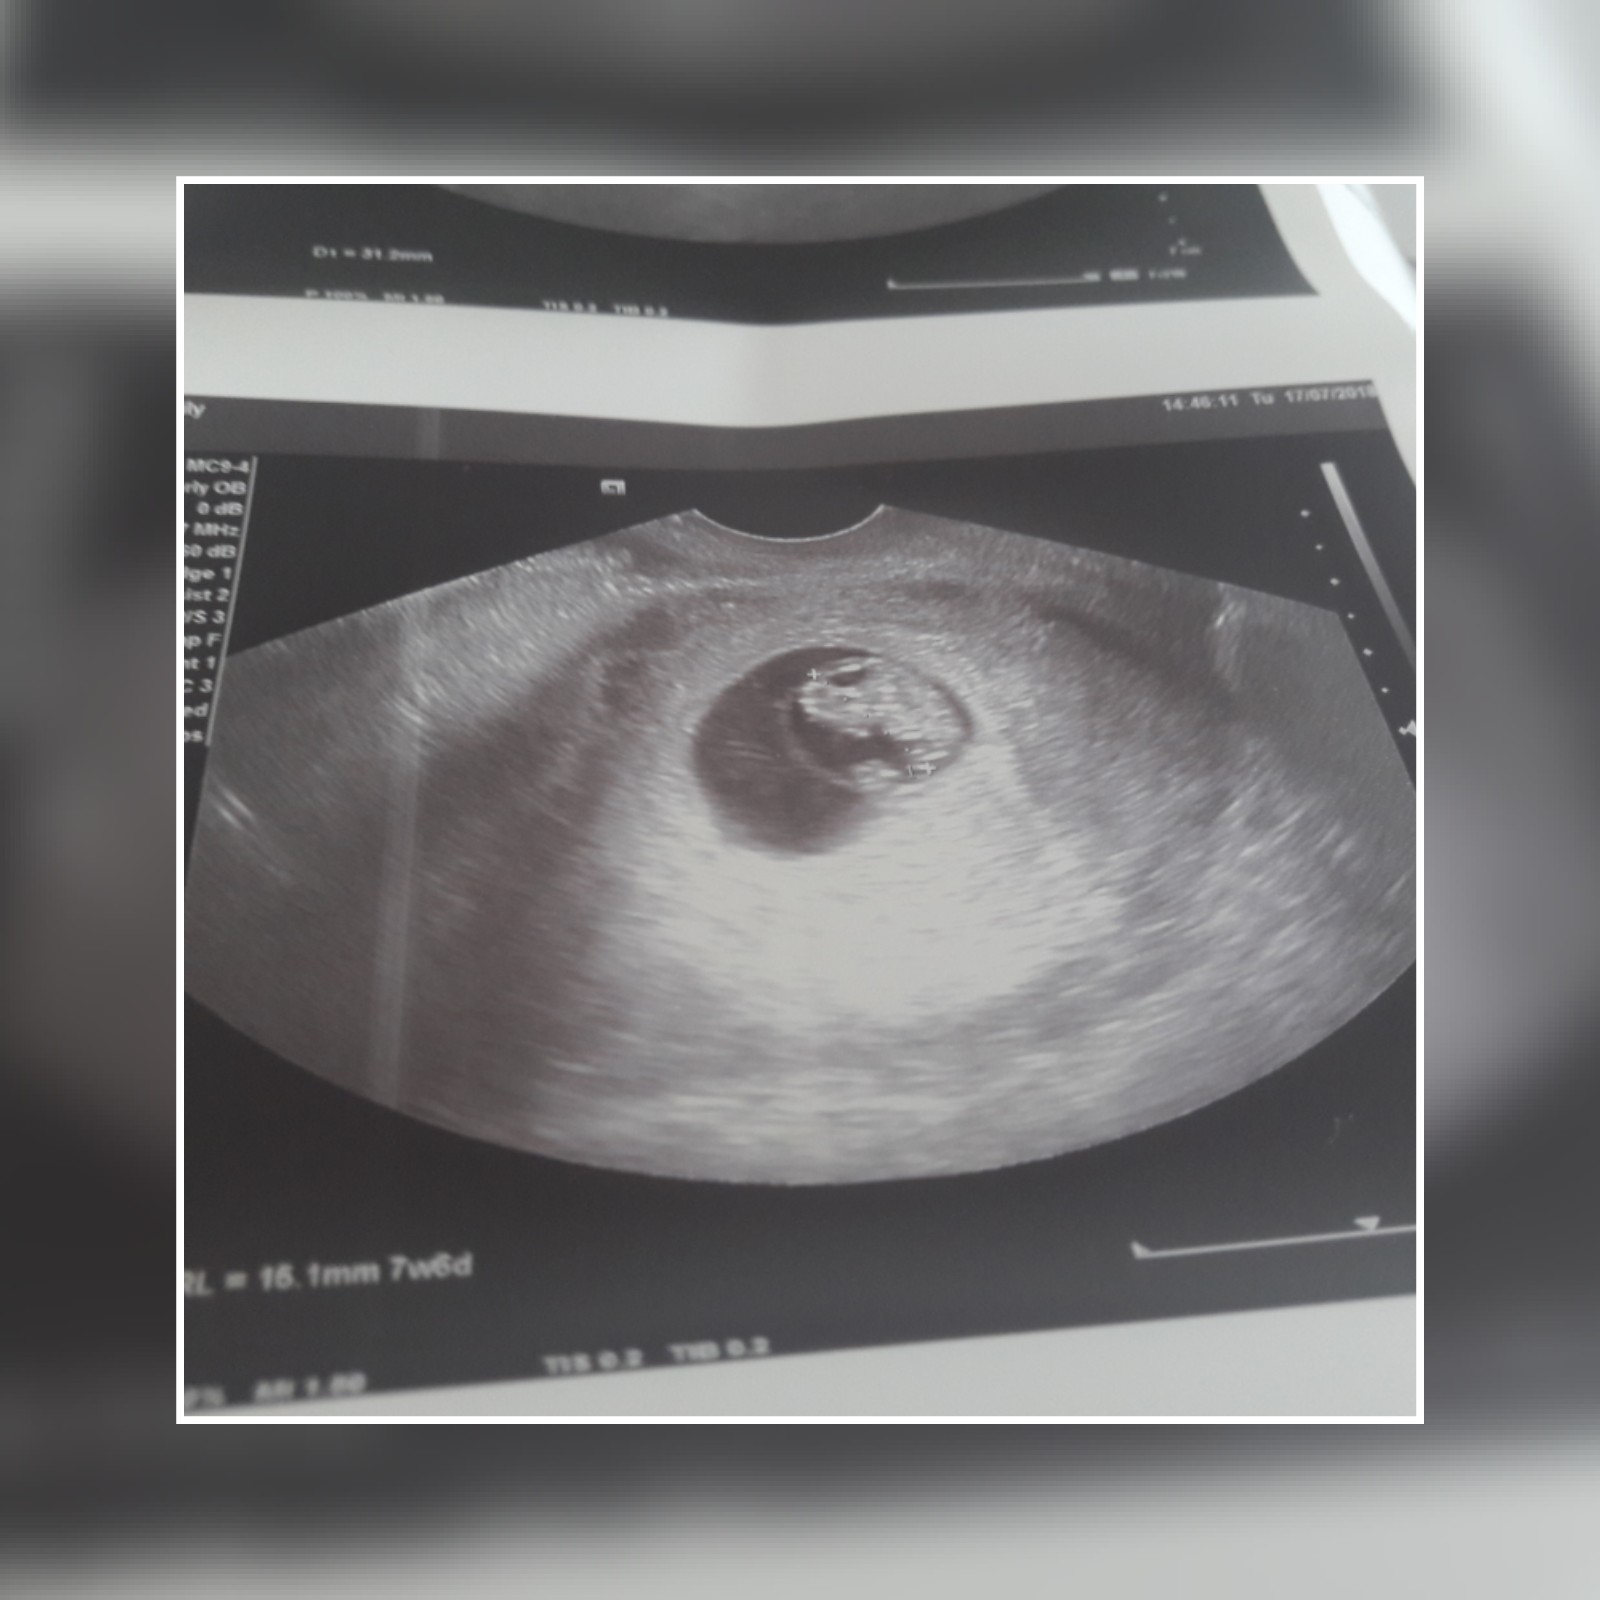

Ale cudne wieści [emoji7] Super, gratuluję i trzymam mocno kciuki żeby tym razem było już tylko dobrze!!!Ja tak na szybko do Was wpadlam :-) ogolnie nie obylo sie bez przygod (miałam plamienia) ale na ten moment wszystko ok ;-)

Dzidzia ma 1,5 cm i ma się dobrze! Zaczęłam juz 9tc.

I jeszcze fotka z wczorajszego usg